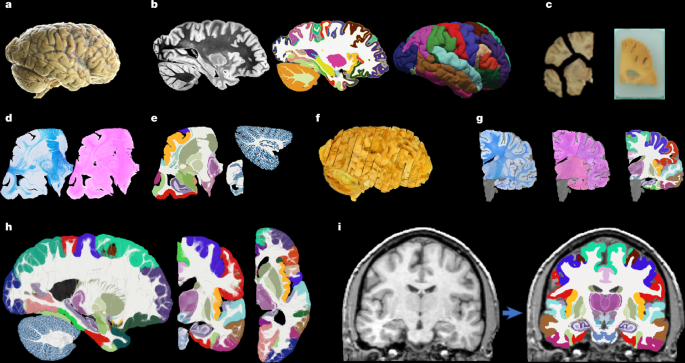

Hemispheres from five individuals (including half of the cerebrum, cerebellum and brainstem), were used in this study, following informed consent to use the tissue for research and the ethical approval for research by the National Research Ethics Service Committee London – Central. All hemispheres were fixed in 10% neutral buffered formalin (Fig. 1a). The laterality and demographics are summarized in Supplementary Table 1; the donors were neurologically normal, but one case had an undiagnosed, asymptomatic tumour (diameter roughly 10 mm) in the white matter, adjacent to the pars opercularis. This tumour did not pose issues in any of the processing steps described below.

Before dissection, the hemispheres were scanned on a 3-T Siemens MAGNETOM Prisma scanner. The specimens were placed in a container filled with Fluorinert (perfluorocarbon), a proton-free fluid with no MRI signal that yields excellent ex vivo MRI contrast and does not affect downstream histological analysis58. The MRI scans were acquired with a T2-weighted sequence (optimized long echo train 3D fast spin echo59) with the following parameters: TR = 500 ms, TEeff = 69 ms, BW = 558 hertz per pixel, echo spacing = 4.96 ms, echo train length = 58, 10 averages, with 400-μm isotropic resolution, acquisition time for each average = 547 s, total scanning time = 91 min. These scans were processed with a combination of SAMSEG35 and the FreeSurfer 7.0 cortical stream51 to bias-field-correct the images, generate rough subcortical segmentations and obtain white matter and pial surfaces with corresponding parcellations according to the Desikan–Killiany atlas29 (Fig. 1b).

After MRI scanning, each hemisphere is dissected to fit into standard 74 mm × 52 mm cassettes. First, each hemisphere was split into cerebrum, cerebellum and brainstem. Using a metal frame as a guide, these were subsequently cut into 10-mm-thick slices in coronal, sagittal and axial orientation, respectively. These slices were photographed inside a rectangular frame of known dimensions for pixel size and perspective correction; we refer to these images as ‘whole slice photographs’. Although the brainstem and cerebellum slices all fit into the cassettes, the cerebrum slices were further cut into as many blocks as needed. ‘Blocked slice photographs’ were also taken for these blocks (Fig. 1c, left).

After standard tissue processing steps, each tissue block was embedded in paraffin wax and sectioned with a sledge microtome at 25-μm thickness. Before each cut, a photograph was taken with a 24 MPx Nikon D5100 camera (ISO = 100, aperture = f/20, shutter speed = automatic) mounted right above the microtome, pointed perpendicularly to the sectioning plane. These photographs (henceforth ‘blockface photographs’) were corrected for pixel size and perspective using fiducial markers. The blockface photographs have poor contrast between grey and white matter (Fig. 1c, right) but also negligible nonlinear geometric distortion, so they can be readily stacked into 3D volumes. A two-dimensional convolutional neural network (CNN) pretrained on the ImageNet dataset60 and fine-tuned on 50 manually labelled examples was used to automatically produce binary tissue masks for the blockface images.

We mounted on glass slides and stained two consecutive sections every N (see below), one with H&E and one with LFB (Fig. 1d). The sampling interval was N = 10 (that is, 250 μm) for blocks that included subcortical structures in the cerebrum, medial structures of the cerebellum or brainstem structures. The interval was N = 20 (500 μm) for all other blocks. All stained sections were digitized with a flatbed scanner at 6,400 DPI resolution (pixel size 3.97 μm). Tissue masks were generated using a two-dimensional CNN similar to the one used for blockface photographs (pretrained on ImageNet and fine-tuned on 100 manually labelled examples).

Dense labelling of histology

To roughly initialize the 3D reconstruction, we relied on the stacks of blockface photographs. Specifically, we used our previously presented hierarchical joint registration framework23 that seeks to (1) align each block to the MRI with a similarity transform, by maximizing the normalized cross-correlation of their intensities while (2) discouraging overlap between blocks or gaps in between, by means of a differentiable regularizer. The similarity transforms allowed for rigid deformation (rotation, translation), as well as isotropic scaling to model the shrinking due to tissue processing. The registration algorithm was initialized with transforms derived from the whole slice, blocked slice and blockface photographs (see details in ref. 26). The registration was hierarchical in the sense that groups of transforms were forced to share the same parameters in the earlier iterations of the optimization, to reflect our knowledge of the cutting procedure. In the first iterations, we clustered the blocks into three groups: cerebrum, cerebellum and brainstem. In the following iterations, we clustered the cerebral blocks that were cut from the same slice and allowed translations in all directions, in-plane rotation and global scaling. In the final iterations, each block alignment was optimized independently. The numerical optimization used the LBFGS algorithm63. The approximate average error after this procedure was about 2 mm (ref. 23). A sample 3D reconstruction is shown in Fig. 1f.

Running SbR for each stain and section independently (that is, LFB to resampled MRI and H&E to resampled MRI) yields a reconstruction that is jagged and sensitive to folds and tears. One alternative is to register each histological section to each neighbour directly, which achieves smooth reconstructions but incurs the so-called ‘banana effect’: that is, a straightening of curved structures14. We have proposed a Bayesian method that yields smooth reconstructions without the banana effect25. This method follows an overconstrained strategy by computing registrations between LFB and MRI, H&E and MRI, H&E and LFB, each LFB section and the two nearest neighbours in either direction across the stack, each H&E section and its neighbours, and each MRI slice and its neighbours. For a stack with S sections, this procedure yields 15xS-18 registrations, whereas the underlying dimensionality of the spanning tree connecting all the images is just 3xS-1. We use a probabilistic model of SVFs to infer the most likely spanning tree given the computed registrations, which are seen as noisy measurements of combinations of transforms in the spanning tree. The probabilistic model uses a Laplace distribution, which relies on L1 norms and is thus robust to outliers. Moreover, the properties of SVFs enable us to write the optimization problem as a linear program, which we solve with a standard simplex algorithm71. The result of this procedure was a 3D reconstruction that is accurate (it is informed by many registrations), robust and smooth (Figs. 1g and 2).

Every iteration of the atlas construction process comprises two steps. First, the current estimate of the atlas and the segmentations are coregistered one at a time using (1) a diffeomorphic deformation model based on SVFs parameterized by grids of control points and B-splines (as implemented in NiftyReg72), which preserves the topology of the segmentations; (2) a data term, which is the log-likelihood of the label at each voxel according to the probabilities given by the deformed atlas (with a weak Dirichlet prior to prevent logs of zero); and (3) a regularizer based on the bending energy of the field, which encourages regularity in the deformations. The second step of each iteration updates the atlas by averaging the segmentations. The procedure converged (negligible change in the atlas) after five iterations. Slices of the atlas are shown in Figs. 1h and 3.

Sample segmentations with this method can be found in Fig. 1h (in vivo) and Fig. 4 (ex vivo).